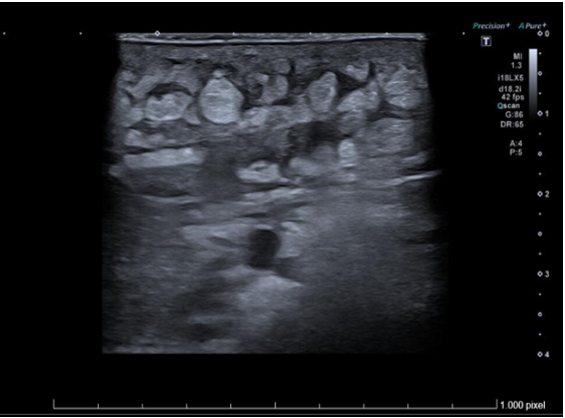

Ecografía de partes blandas de axila izquierda: Piel engrosada con aspecto hipoecogénico y heterogéneo. Tejido celular subcutáneo con cambios inflamatorios y edema, que simula imagen en forma de nubes. Colección de 13x36 mm en tejido celular subcutáneo con márgenes irregulares, contenido ecogénico fluctuante con trazos hiperecogénicos periféricos. Vasos regionales permeables sin signos de trombosis. Hallazgos compatibles con absceso subcutáneo y celulitis.